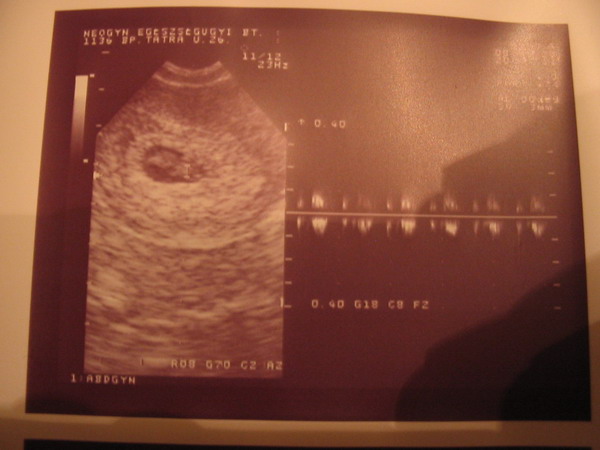

Gyonyoru szep baboca!!!!!!!!